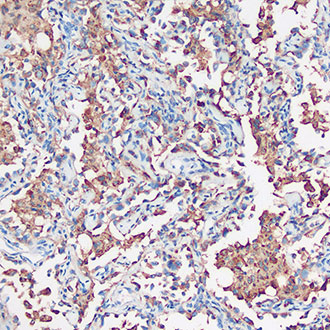

Napsin A

Napsin A -